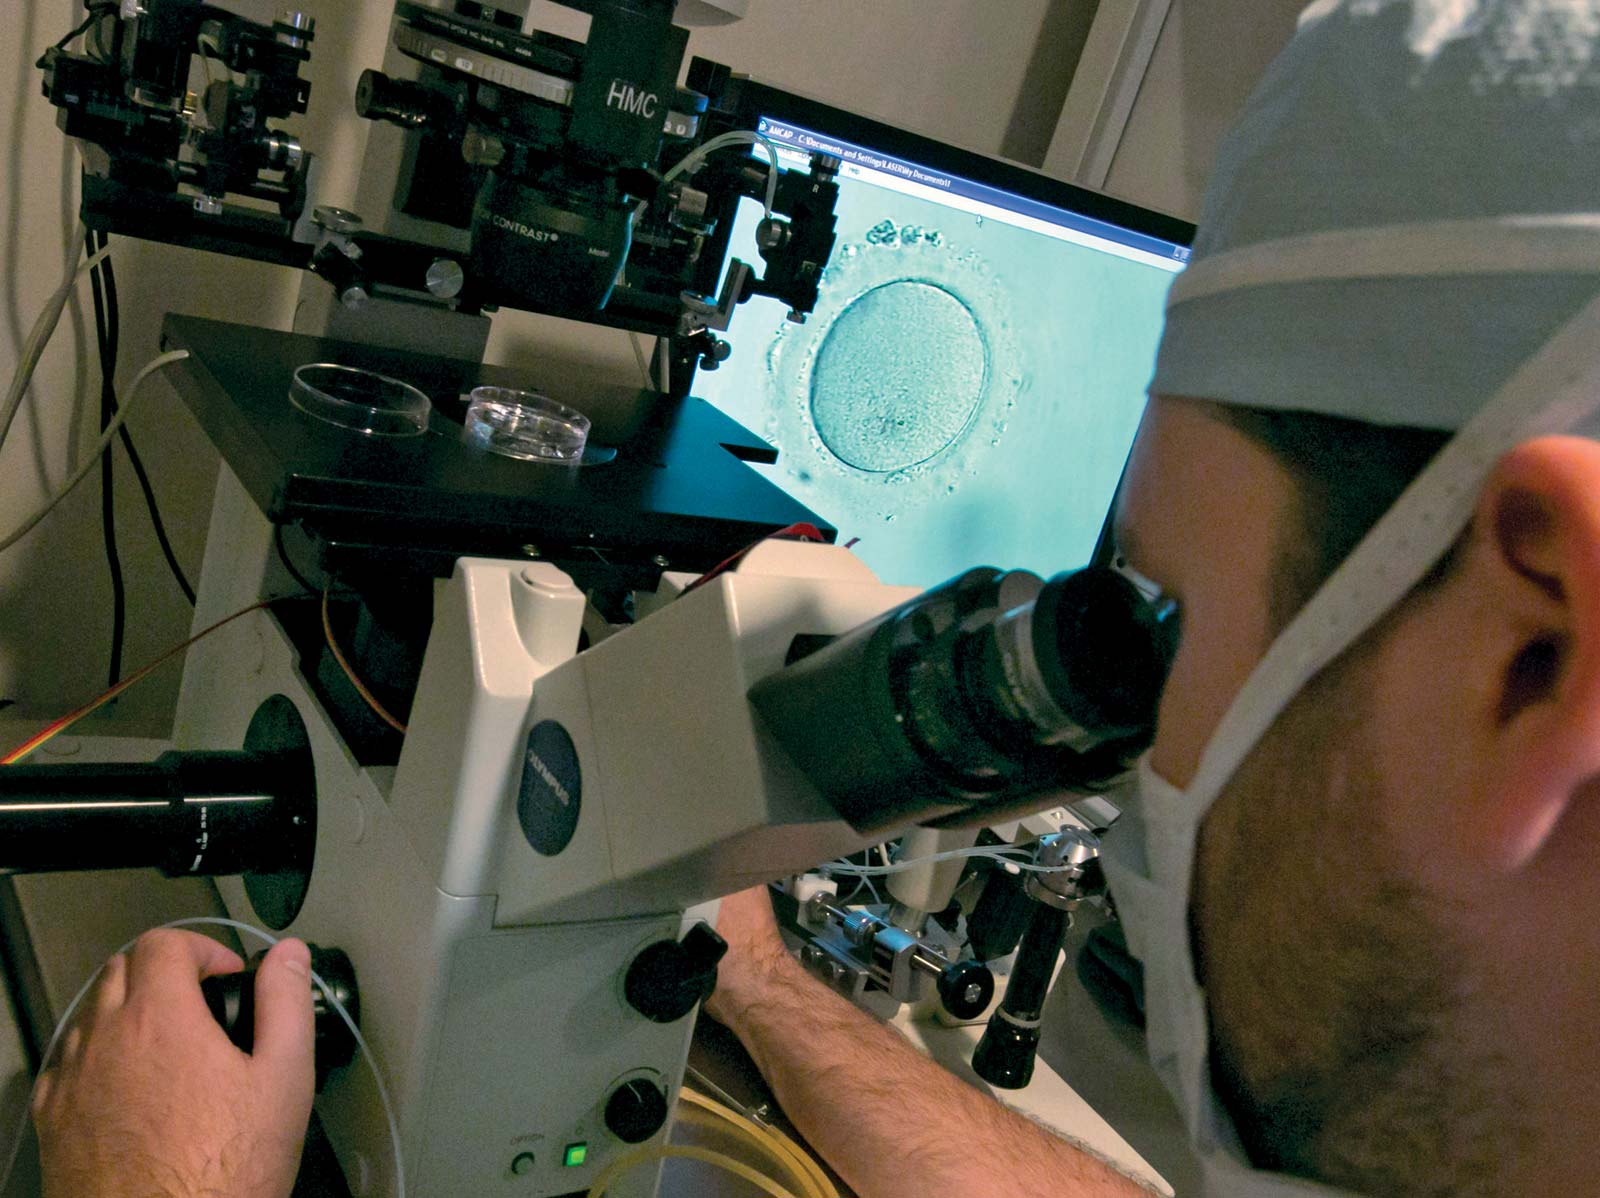

Os recursos da medicina moderna para vencer a infertilidade de Paulo Eduardo Olmos: Utiliza uma abordagem simples e acessível para apresentar uma abordagem completa das causas, exames e tratamentos da infertilidade masculina e feminina. Mostra que a realização de um diagnóstico minucioso é crucial para o sucesso do tratamento e para a conquista do tão sonhado bebê. De grande contribuição para os inúmeros casais que, desejando um filho, não conseguem compreender totalmente as causas, complexidades e tratamentos da infertilidade conjugal através da reprodução assistida.